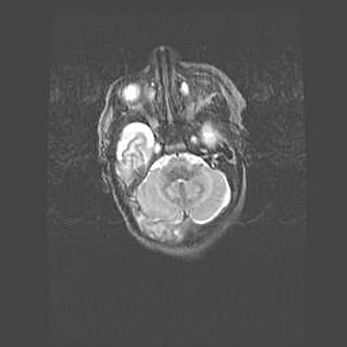

Подострая гематома правой гемисферы мозжечка.

Наружная гидроцефалия.

Возраст: 15 дней

Вес: 3100 г

Пол: женский

Окружность головы: 37 см

Срок гестации: 35-36 недель

При открытой наружной форме гидроцефалии у новорожденных расширяются и переполняются субарахноидные пространства.

Кровоизлияния в мозжечок имеют две клинико-анатомические формы: полушарные гематомы и кровоизлияния в червь.

К появлению этой патологии может привести: повреждения головного мозга, возникающие в результате асфиксии и гипоксии плода при беременности, или травмы во время родов. Редко гематома мозжечка может быть результатом первичной коагулопатии и сосудистой мальформации, диссеминированном внутрисосудистом свертывании, изоиммунной тромбоцитопении.